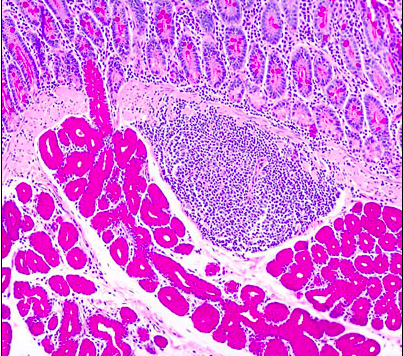

Name the cells bordering the lumen [1]

paneth cell

what region of the GI tract is this? [1]

how can you tell? [1]

duodenum [1]

brunners glands [1]